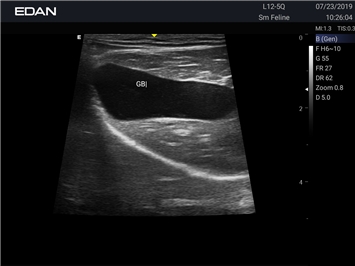

EDAN Acclarix AX2 VET

Ветеринарный ультразвук одним нажатием. Система Acclarix AX2 VET разработана с целью обеспечить бескомпромиссную производительность по доступной цене. Наличие уникальных двойных аккумуляторов в легком корпусе массой 4,5 кг из магниевого сплава позволяет системе Acclarix AX2 VET удовлетворять все потребности ветеринарных исследований, сохранив низкую стоимость.

EDAN Acclarix AX2 VET представляет собой специализированную ветеринарную ультразвуковую систему, сочетающую высокую производительность с доступной ценой. Благодаря продуманной конструкции и передовым технологиям, система обеспечивает качественную диагностику животных различных видов.